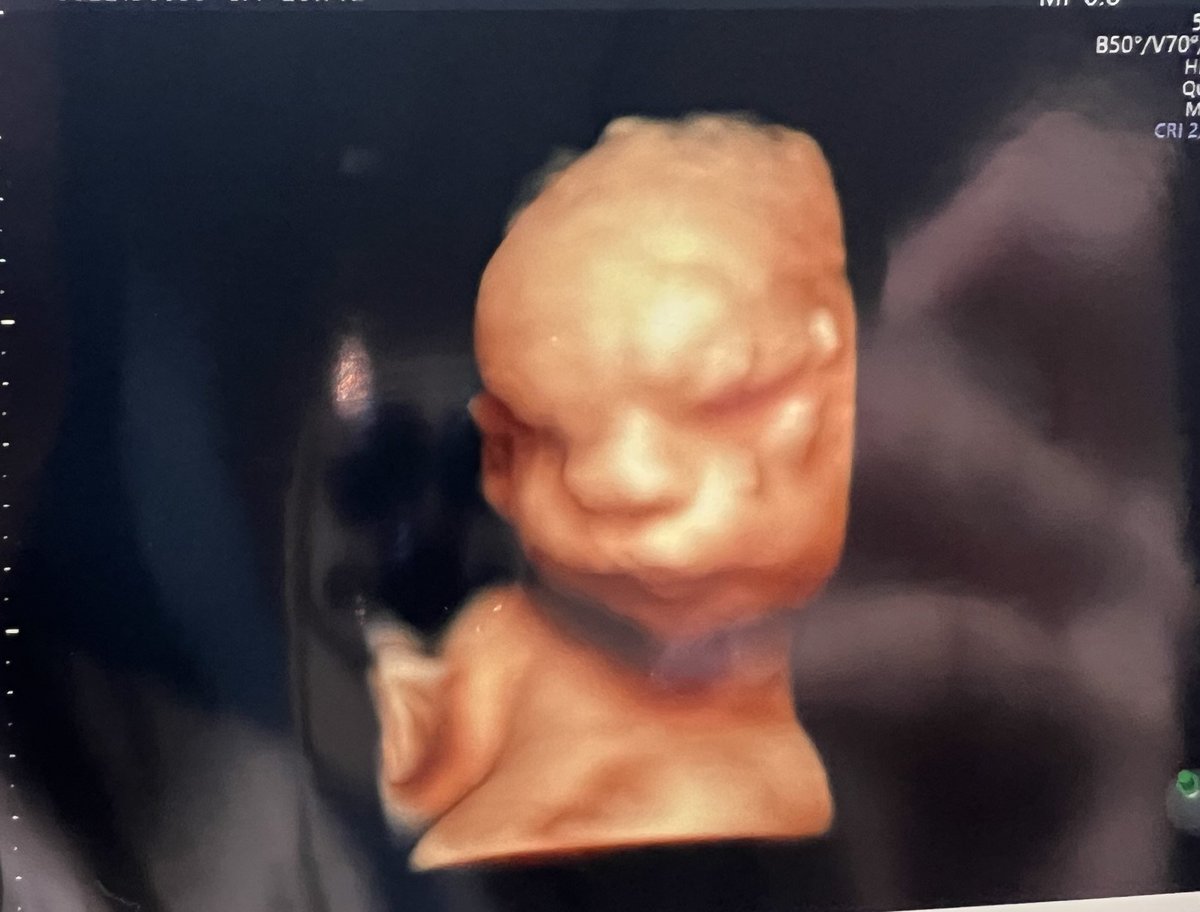

妊娠28週(妊娠8か月)のころのエコー画像

8/28